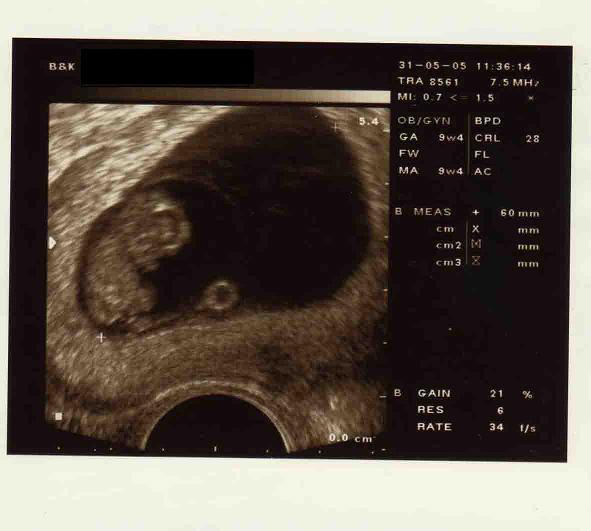

to jest usg mojego dziecka w 9 tygodniu ciazy... mozna je zaliczyc jako istote ludzka czy ''zlepek komorek''? posiada juz glowe tulow rece i nogi a takze serce...

ale superr zdjęcie Widać już dzidziunia i to bardzo wyraźnie

dkoladnie a ma tylko 9 tygodni...